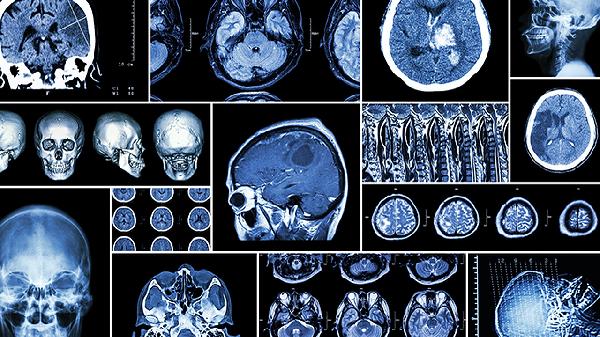

脑部核磁共振能检测出什么疾病呢

脑部核磁共振MRI是一种先进且无创的影像学检查方法,能够清晰显示脑部结构,帮助诊断多种疾病,包括脑肿瘤、脑血管疾病、脑炎、多发性硬化症和阿尔茨海默病等。它是检测脑部疾病的重要手段,结合临床症状可以更准